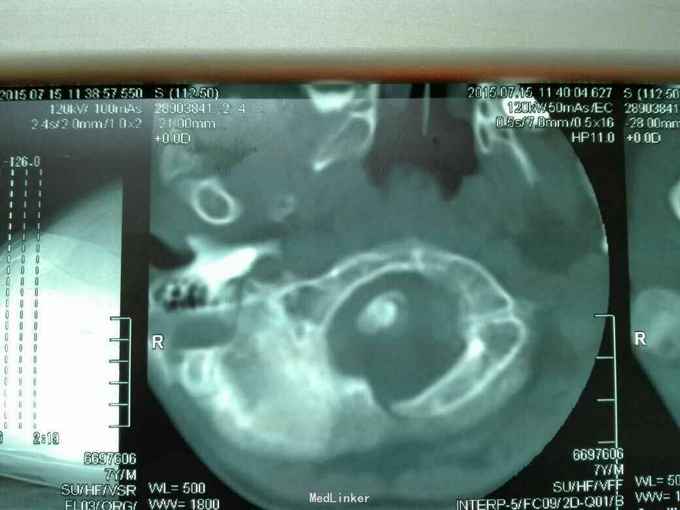

先天脊柱畸形

先天脊柱畸形8年。